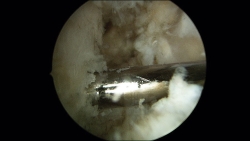

Una vez realizados los 2 túneles, desde el portal anterolateral se inserta el tornillo de biotenodesis de 5 × 15 mm con la plastia colocada hasta la punta del destornillador y se inserta el tornillo siguiendo la técnica (Figura 6).

Figura 6. Tornillo de biotenodesis con la plastia colocada y lista para su introducción.

Una vez colocados los 2 tornillos, se puede objetivar la estabilidad de la plastia intraarticularmente con el artroscopio y externamente con un gentil movimiento varo-valgo (Figura 8).

Figura 8. Plastia una vez realizado el bloqueo a nivel del astrágalo. Resultado final.